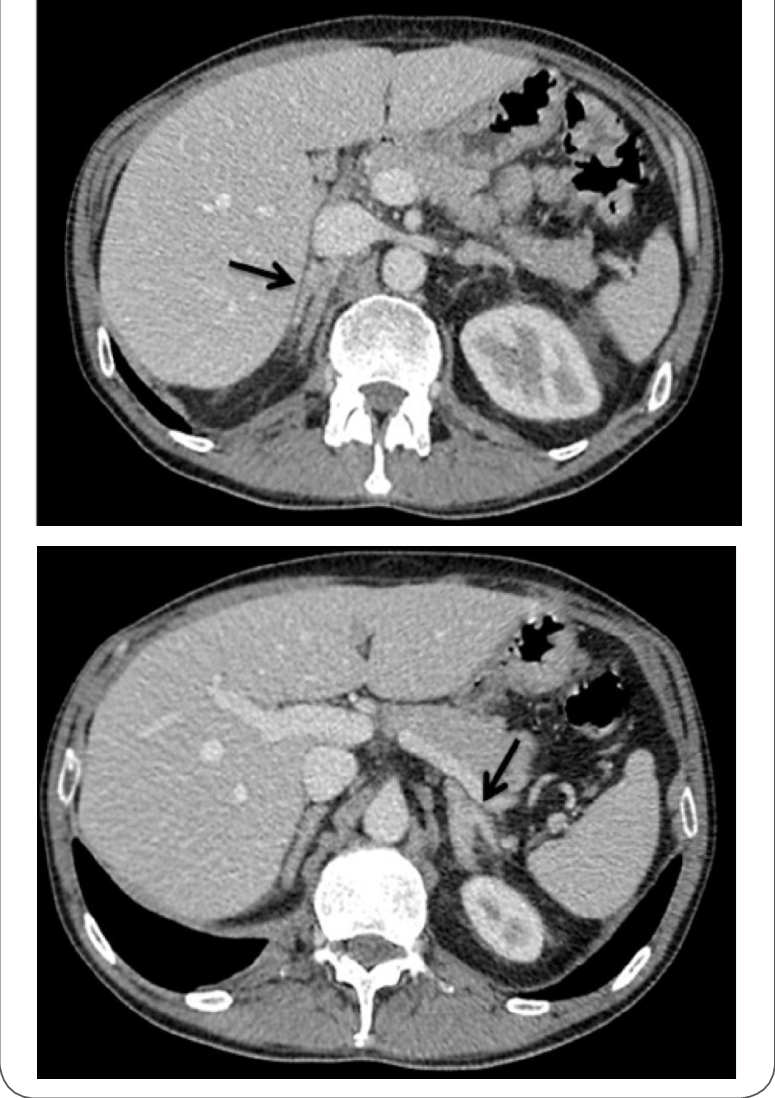

Hyperaldosteronism has been diagnosed historically by Adrenal Venous Sampling. It’s accomplished by running a catheter through the femoral vein up to each of the adrenal veins and sampling blood as it leaves the adrenal tissue. The amount and proportions of cortisol and aldosterone are compared. The method carries a risk of producing venal thrombosis and misdiagnosis is possible. If a diagnosis is made adenomas can be removed by laproscopic surgery. Bilateral hyperplasias can’t be removed surgically and need to be treated by medication and lifestyle. The CT images at the bottom of this post show the difference between the two, and demonstrate how difficult visual diagnosis can be.